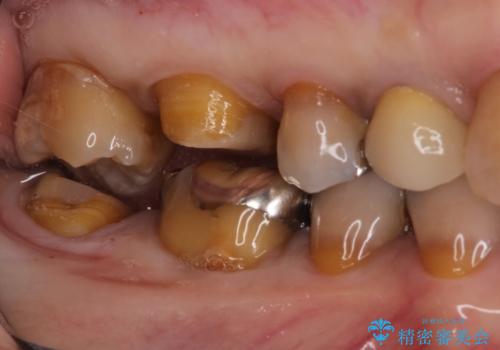

- 他院で入れたセラミックインレーがかけたことを主訴に来院されました。

他の部位にもむし歯を認めたため、優先度の高い歯から治療を行っております。

咬合力が強くかかる部分には欠けるリスクのほとんどない金属を用いることが最良ですが審美性に劣ります。

今回は白い材料での修復を希望されたため、欠けるリスクが高いセラミックインレーは避け、セラミッククラウンにて治療を行いました。